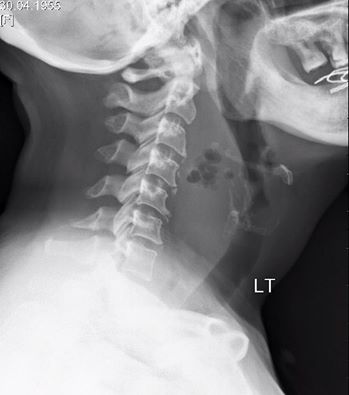

Q: Diabetic woman w neck pain 4 days after swallowing fish bone Diagnosis? ANSWER: goo.gl/gG75HQ #FOAMed

RadiologySigns's tweet image. Q: Diabetic woman w neck pain 4 days after swallowing fish bone Diagnosis?

ANSWER: goo.gl/gG75HQ #FOAMed